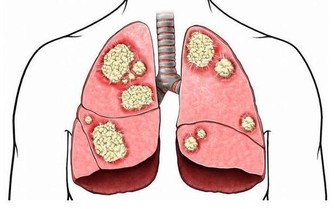

(2)引發腎病

高尿酸血症可導致急性尿酸性腎病、慢性尿酸性腎病和腎結石,增加發生腎功能衰竭的風險,而腎功能不全又是高尿酸血症和痛風的重要危險因素。